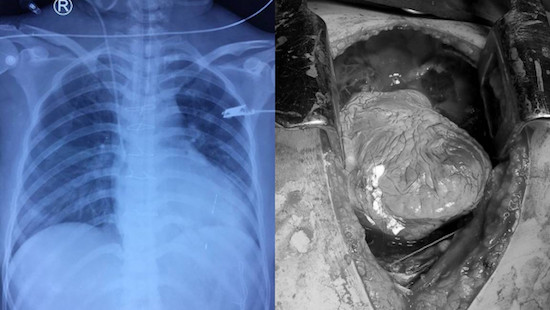

Theo đó, vào đêm 10/12, chị N.T.A. (35 tuổi; ngụ huyện Đức Hòa, tỉnh Long An) được vào cấp cứu trong đêm trong tình trạng có 1 vết đâm vào giữa xương ức và 1 vết đâm ở ngực trái; da và niêm mạc trắng nhợt, lơ mơ, mạch khó bắt, huyết áp không đo được.

Xác định vết thương thấu ngực sốc mất máu nặng, khả năng thủng tim rất cao, có thể kèm tổn thương ở ổ bụng, nguy cơ tử vong rất cao, các bác sĩ liên Khoa Tim mạch – Lồng ngực và Khoa Ngoại tổng quát của Bệnh viện Đa khoa Xuyên Á phẫu thuật khẩn cấp.

Ngay khi mở ngực, các phẫu thuật viên Tim mạch – Lồng ngực phát hiện tim bệnh nhân bị chèn ép cấp do tràn máu màng tim lượng nhiều, khi mở màng ngoài tim, phát hiện vết thương tim thủng thất phải gây cắt đứt một nhánh bờ phải của động mạch vành phải và đang phun máu ồ ạt. Trong tình trạng ấy, các phẫu thuật viên vừa dùng tay bịt vết thương cầm máu tạm thời, vừa khâu lại vết thương tim.

Bên cạnh đó, nạn nhân còn bị thủng cơ hoành, đứt tĩnh mạch gây tràn máu ổ bụng. Lưỡi dao đâm xuyên ra sau làm thủng gan, tổn thương tĩnh mạch trên gan.